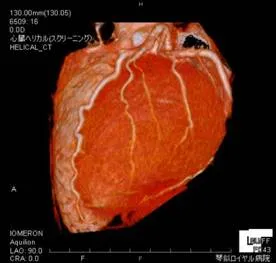

冠動脈CT

CT検査は全身の臓器の状態を調べることが出来る検査で、以前から幅広く医療現場で使われています。 しかし、心臓は絶え間なく動いている臓器なので、これまではCTで心臓を撮影することが困難でした。 近年、CTの性能が向上したことで心臓にも応用されています。特に、心臓へ血液を送る冠動脈を撮影することが出来るようになったため、狭心症や心筋梗塞といった虚血性心疾患について調べることが出来るようになりました。 冠動脈CTで異常が認められた場合は、心臓カテー テル検査による精密検査が必要です。

冠動脈CT:VR画像(左)、MIP画像(右)